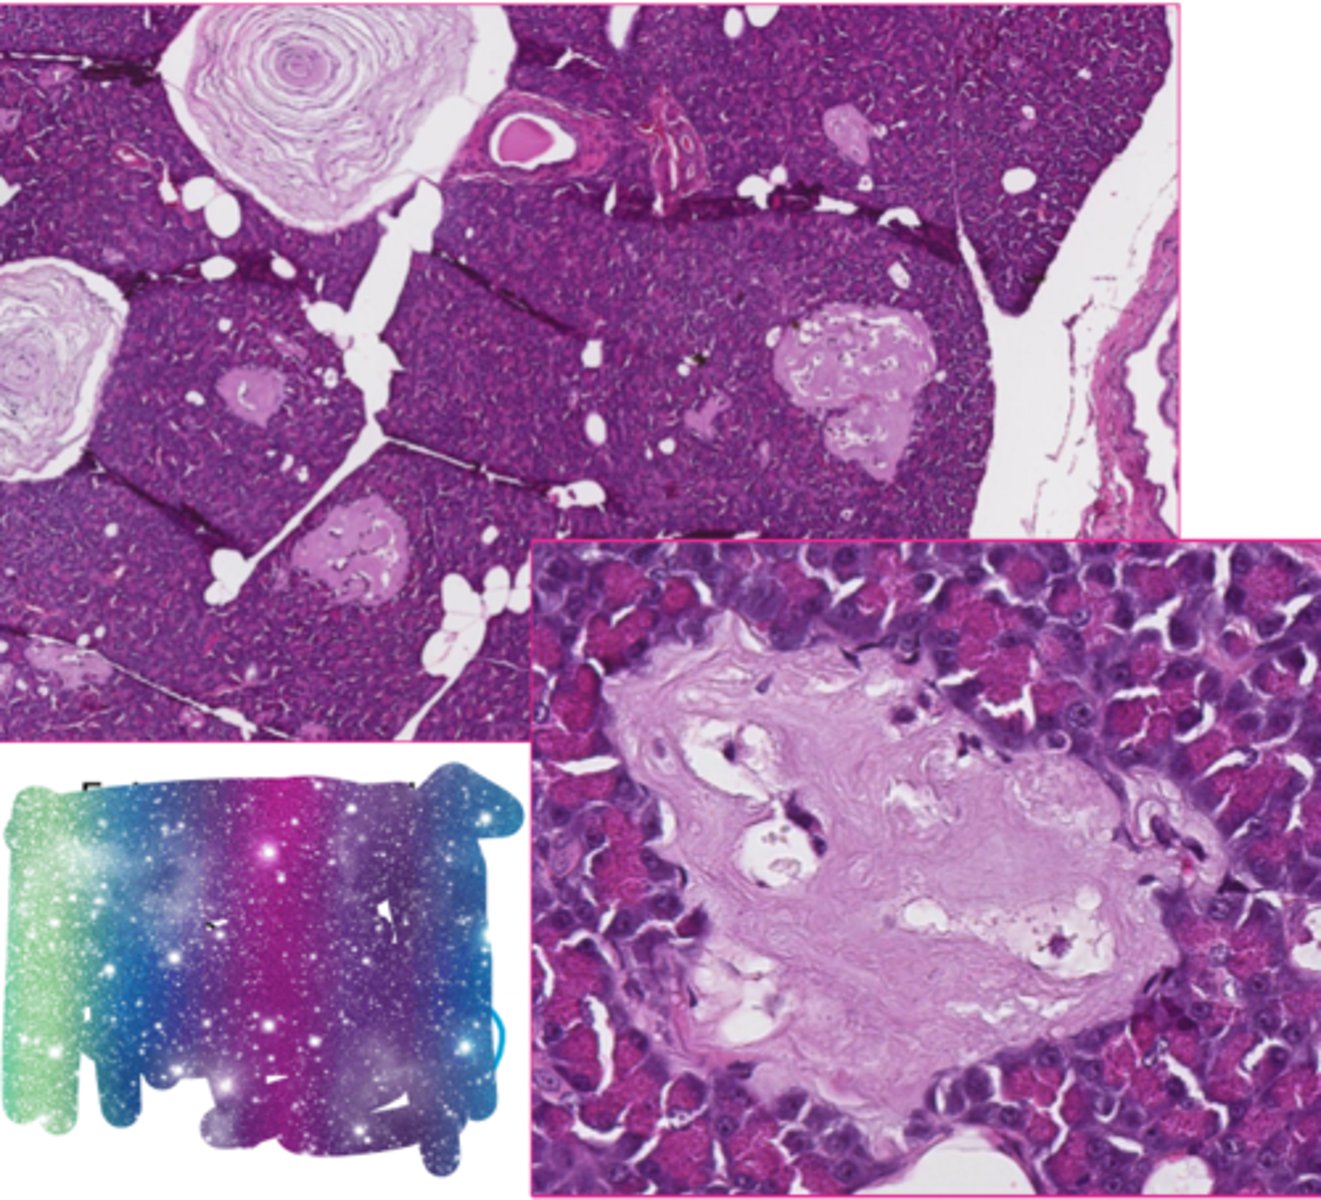

hyaline casts

What extracellular inclusion?

<p>What extracellular inclusion?</p>

8

corpora amylacea